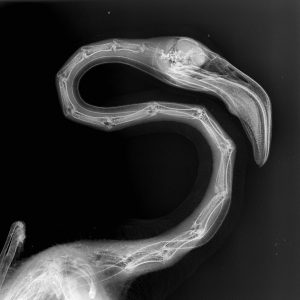

Este procedimiento diagnóstico permite a nuestros expertos brindar una excelente atención médica. Al exponerlos a los rayos X, el equipo puede tomar fotografías de las partes óseas internas de los animales, comprobando la existencia de lesiones o enfermedades que a simple vista no podrían ser identificadas.

Pero, ¿cómo se toma una radiografía de un tigre de Sumatra, de un cálao Gorginegro, un flamenco o un encantador armadillo de tres bandas?